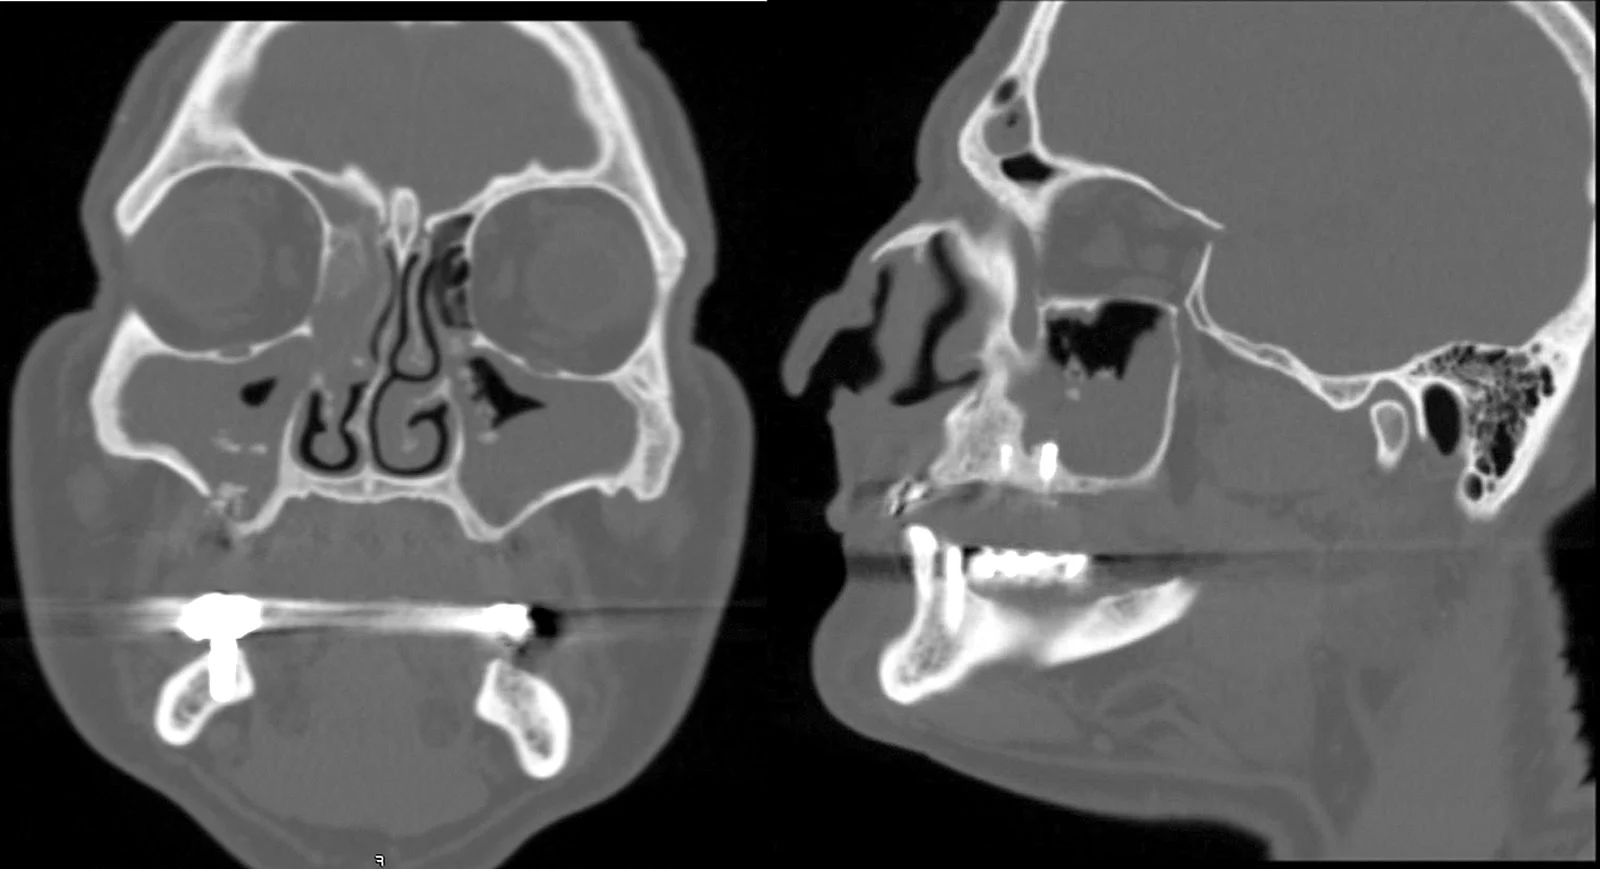

Si eseguono radiografie panoramiche e una TAC Cone Beam (CBCT), indispensabile per visualizzare con precisione la quantità di osso presente nella mascella e la morfologia della cavità nasale.

Viene studiata l’anatomia del mascellare superiore e la posizione dei turbinati, per evitare interferenze anatomiche durante l’inserimento degli impianti.

Attraverso un software di pianificazione 3D, il chirurgo simula virtualmente la procedura, scegliendo la lunghezza, l’inclinazione e il punto d’ingresso ideale degli impianti nasali. Questo riduce drasticamente i margini d’errore intraoperatori.

Secondo il consenso internazionale, l’impianto dovrebbe essere rimosso solo in presenza di sinusite odontogena persistente che non risponde ai trattamenti farmacologici o chirurgici conservativi. In tutti gli altri casi, l’intervento può rappresentare un trauma inutile per il paziente e comportare rischi maggiori rispetto ai benefici. - Importanza della diagnostica avanzata

- Importanza della diagnosi preoperatoria Prima di procedere con l’inserimento di impianti, soprattutto in presenza di atrofie, è fondamentale eseguire una TAC Cone Beam per valutare l’anatomia dei seni paranasali, la presenza di infiammazioni, cisti o varianti anatomiche (come deviazioni del setto o polipi). In presenza di patologie, il paziente deve essere trattato prima dell’intervento implantare.

- L’importanza della pianificazione digitale e TAC 3D Il chirurgo esperto utilizza tecnologie avanzate come la pianificazione computer-guidata, la chirurgia assistita da software 3D e la tomografia Cone Beam (CBCT) per avere una visione completa delle strutture ossee e dei seni paranasali. Questa fase preoperatoria consente di: